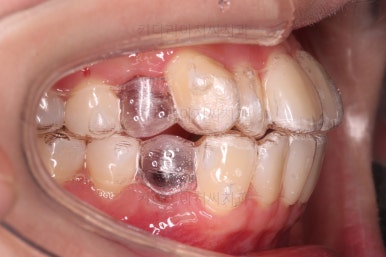

인비절라인을 착용한 모습인데요.

필요한 치아는 발치가 되어 있고요.

눈에는 잘 띄지 않지만 치아 색깔나는 재료로 어태치먼트라고 하는 부착물도 부착되어 있어요. 장치를 잘 잡아주는 손잡이와 같은 역할을 해줍니다.

어금니쪽을 잘 보시면 별표? 혹은 꽃모양 무늬가 그려진게 보이실텐데요.

이 그림이 있는게 인비절라인 정품입니다.

국내외 유사 투명교정 장치가 많이 나오고 있지만 아직은 기술력에서 인비절라인이 가장 앞서 있어서 저희 부산교정전문의 키다리아저씨치과에서는 투명교정은 인비절라인으로 현재 진행하고 있습니다.